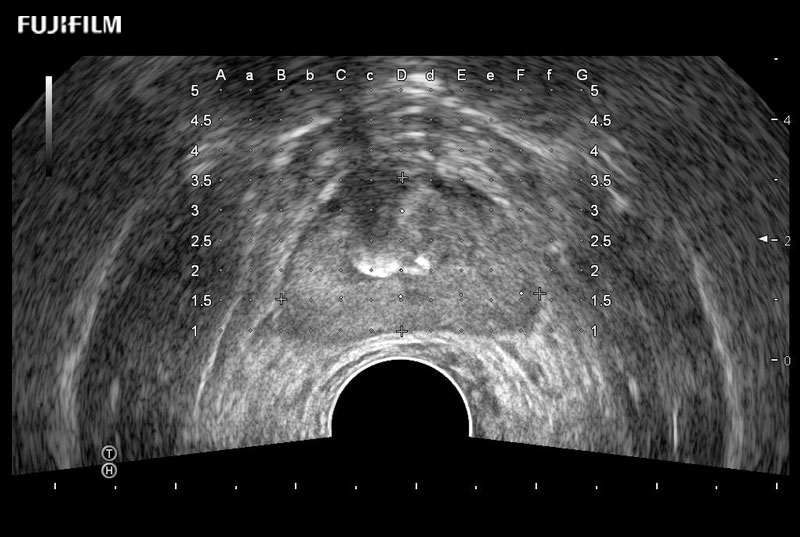

Exclusive 200° FOV end-fire prostate biopsy transducer.

Main Specifications:

Provides real-time imaging of both the sagittal and transverse planes